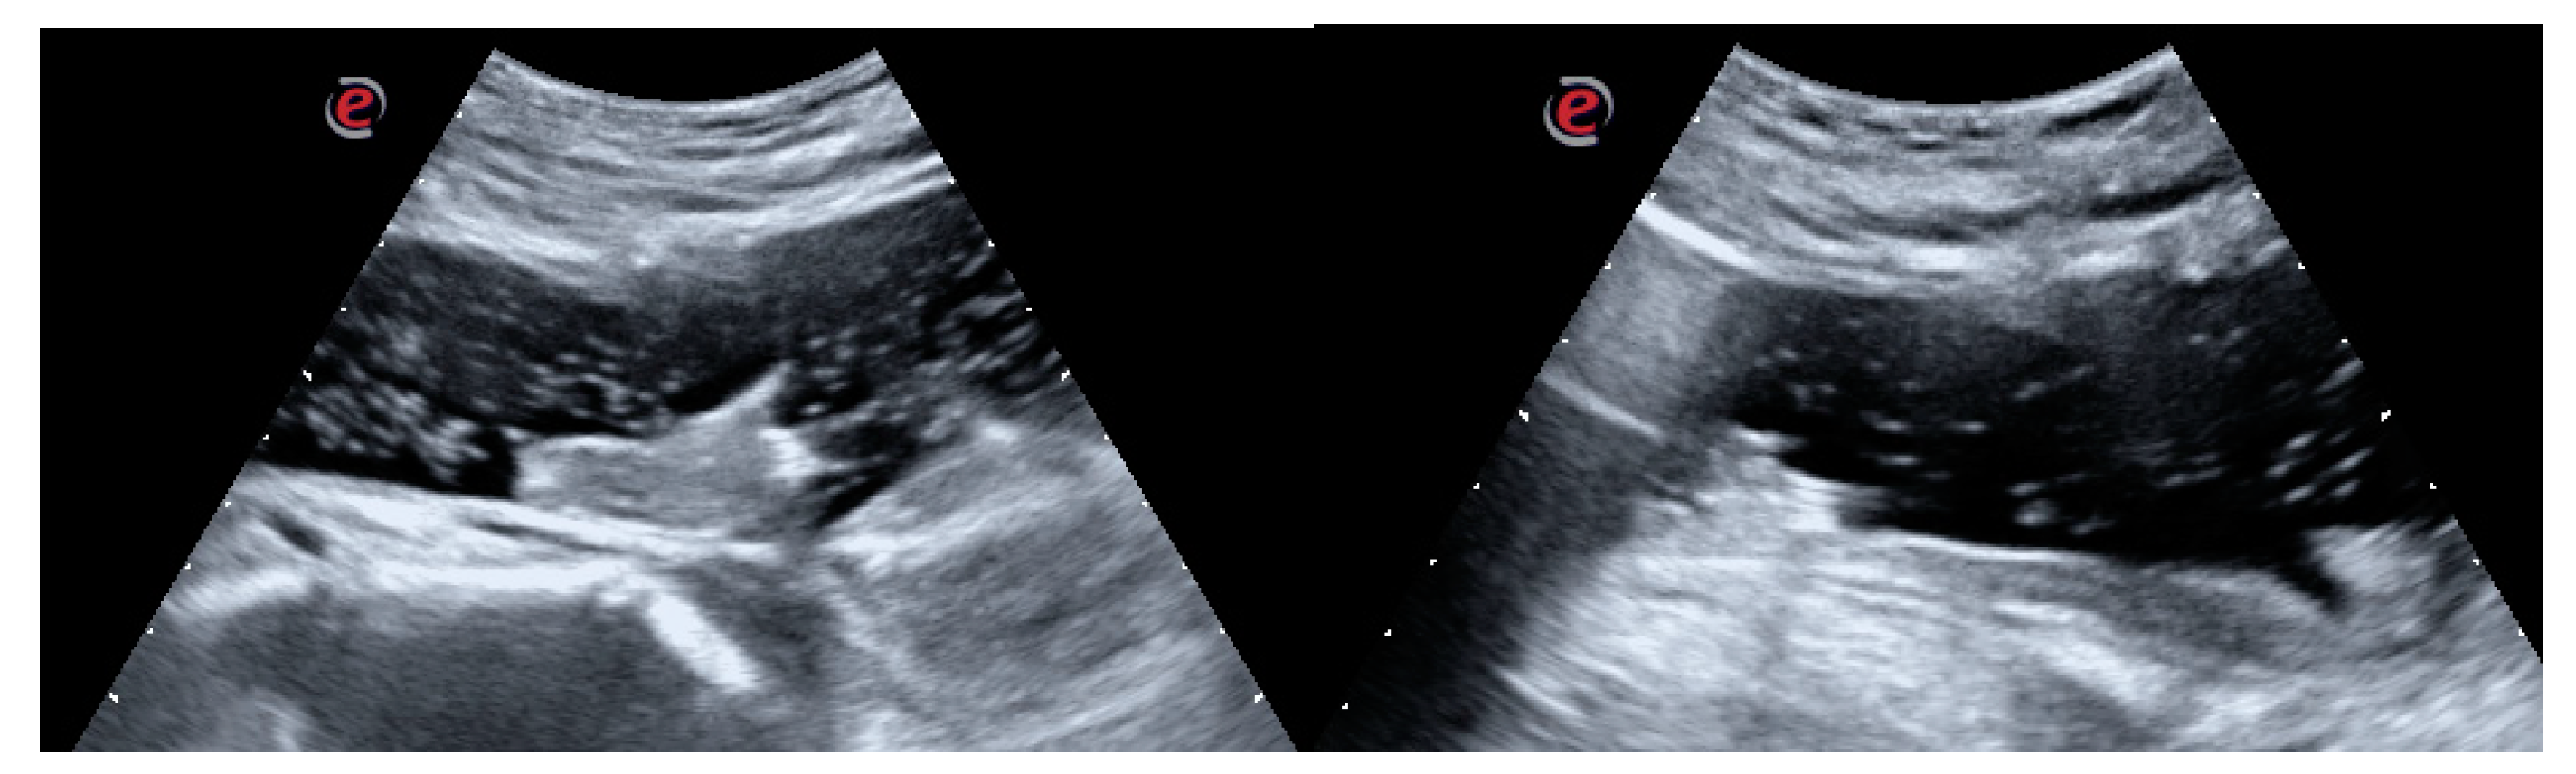

The preliminary endoscopic evaluation confirmed the hematic nature of the clot without any sign of active bleeding (Figure 2a,b).

Figure 2. (a-b) Endoscopic view: endoscopic appearance of the clot. The light red shade of color suggests the late formation of the clot, thus its friability. No signs of active bleeding are visible.